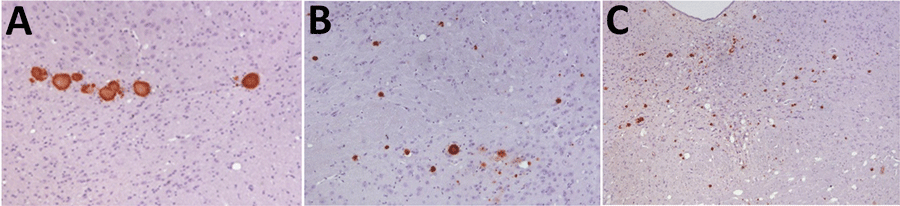

Figure 3. Immunohistochemistry results of brain tissue in study of propagation of classical scrapie prions. Images are of tissue specimens from K222-Tg516 mice inoculated with F10 goat scrapie isolate at second passage. Results are visualized using the Sha31 monoclonal antibody. A) Thalamus specimen. B) Hippocampus specimen. C) Midbrain specimen.